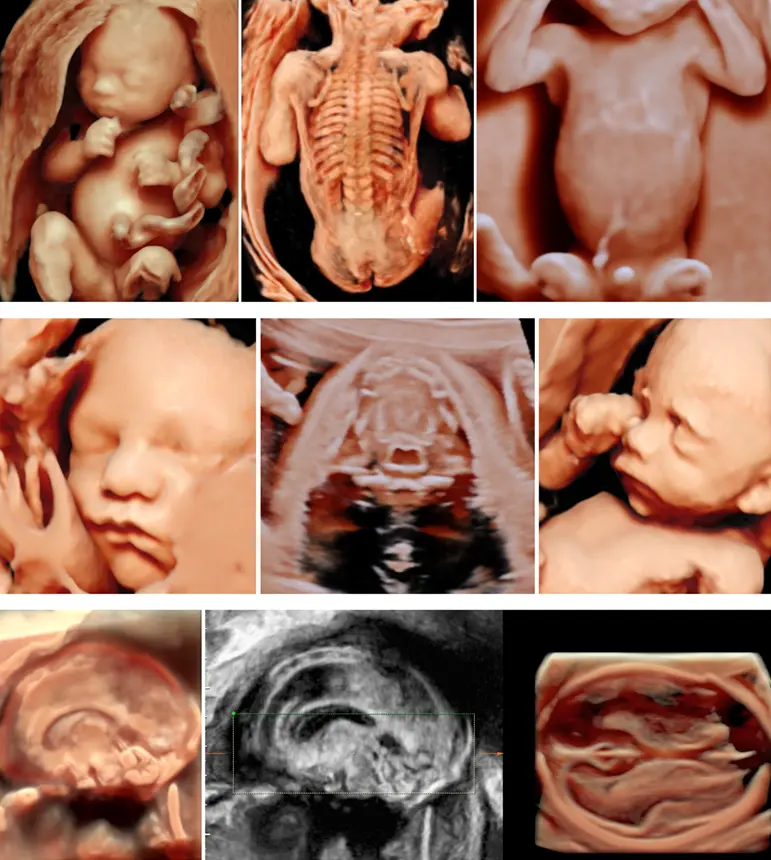

Die Feindiagnostik, auch Fehlbildungsdiagnostik genannt, ist eine spezielle Ultraschalluntersuchung, die während der Schwangerschaft durchgeführt wird. Im Gegensatz zum normalen Ultraschall, der eher einen groben Überblick über die Entwicklung des Fötus gibt, konzentriert sich die Feindiagnostik auf die detaillierte Untersuchung aller wichtigen Organe und Körperstrukturen des Kindes. So können mögliche Fehlbildungen frühzeitig erkannt und gegebenenfalls behandelt werden.

Bei der Feindiagnostik werden alle wichtigen Organe des Fötus untersucht, darunter:

- Gehirn

- Herz

- Wirbelsäule

- Extremitäten

- Bauch

- Magen-Darm-Trakt

- Nieren

- Harnblase

Zusätzlich wird die Plazenta und die Menge des Fruchtwassers begutachtet.